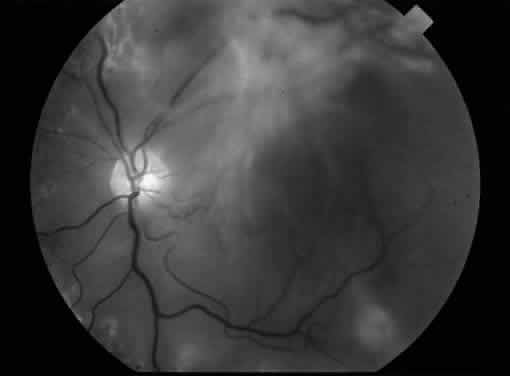

MACULAR TRACTION RETINAL DETACHMENT

The pathogenesis of diabetic traction retinal detachment involves interaction between the posterior hyaloid surface, preretinal fibrovascular proliferation, and the retina. Epiretinal fibrovascular tissue grows along the posterior surface of the vitreous gel. As the fibrovascular tissue contracts, the posterior hyaloid becomes taut and partially separates from the retina. Anteroposterior traction on the remaining areas of vitreoretinal attachment causes tractional retinal detachment. Traction retinal detachments are separated into those where the macula is detached and those where the traction detachment does not involve the macula (Fig. 4). Charles and Flinn studied the natural history of diabetic extramacular traction retinal detachment.18 They found a progression to macular detachment in only 13.8% of eyes at 1-year follow-up. Because most patients with extramacular traction retinal detachments do not progress to involve the macula, vitrectomy is indicated only for patients with traction macular detachment in the absence of significant macular heterotopia or vitreous hemorrhage. In patients with traction macular detachment, surgery should not be deferred for an extended period of time because retinal vascular changes may cause irreversible macular damage, reducing the potential for visual recovery.19 The results of vitrectomy for 360 eyes with diabetic traction retinal detachment of the macula were evaluated.20 Fifty-nine percent of eyes had improved visual acuity on final examination. The percentage of eyes with final visual acuity of 20/100 or better was 36%, and the percentage with a final visual acuity 5/200 or better was 72%. Preoperative factors associated with a favorable visual prognosis included the following: visual acuity of 5/200 or better, absence of iris neovascularization, minimal cataract, mild or no vitreous hemorrhage, panretinal photocoagulation of at least one fourth of the retina, and absence of severe retinal neovascular proliferation. Intraoperative factors associated with a worse visual prognosis included lensectomy, iatrogenic retinal breaks, and use of intraocular gas tamponade.

Fig. 4. An example of an eye with proliferative diabetic retinopathy and traction retinal detachment involving the macula.